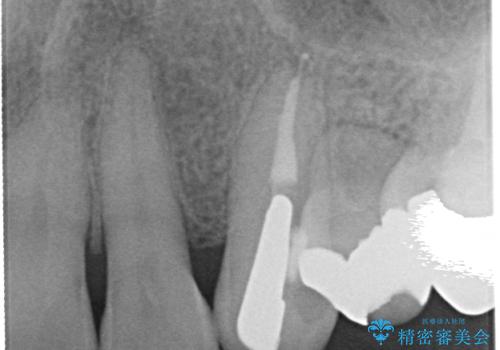

- 他院にて左上3番の被せ物を勧められたが、根管治療からやり直したいと当院にいらっしゃった方の症例です。

再根管治療後、オールセラミッククラウンによる補綴を行いました。

- 根管治療により痛みや腫れがひかない事や、術後に痛みや腫れが生じる事、治療によるファイル破折やパーフォレーションなどの偶発症、術後の歯根破折を生じる可能性もあります